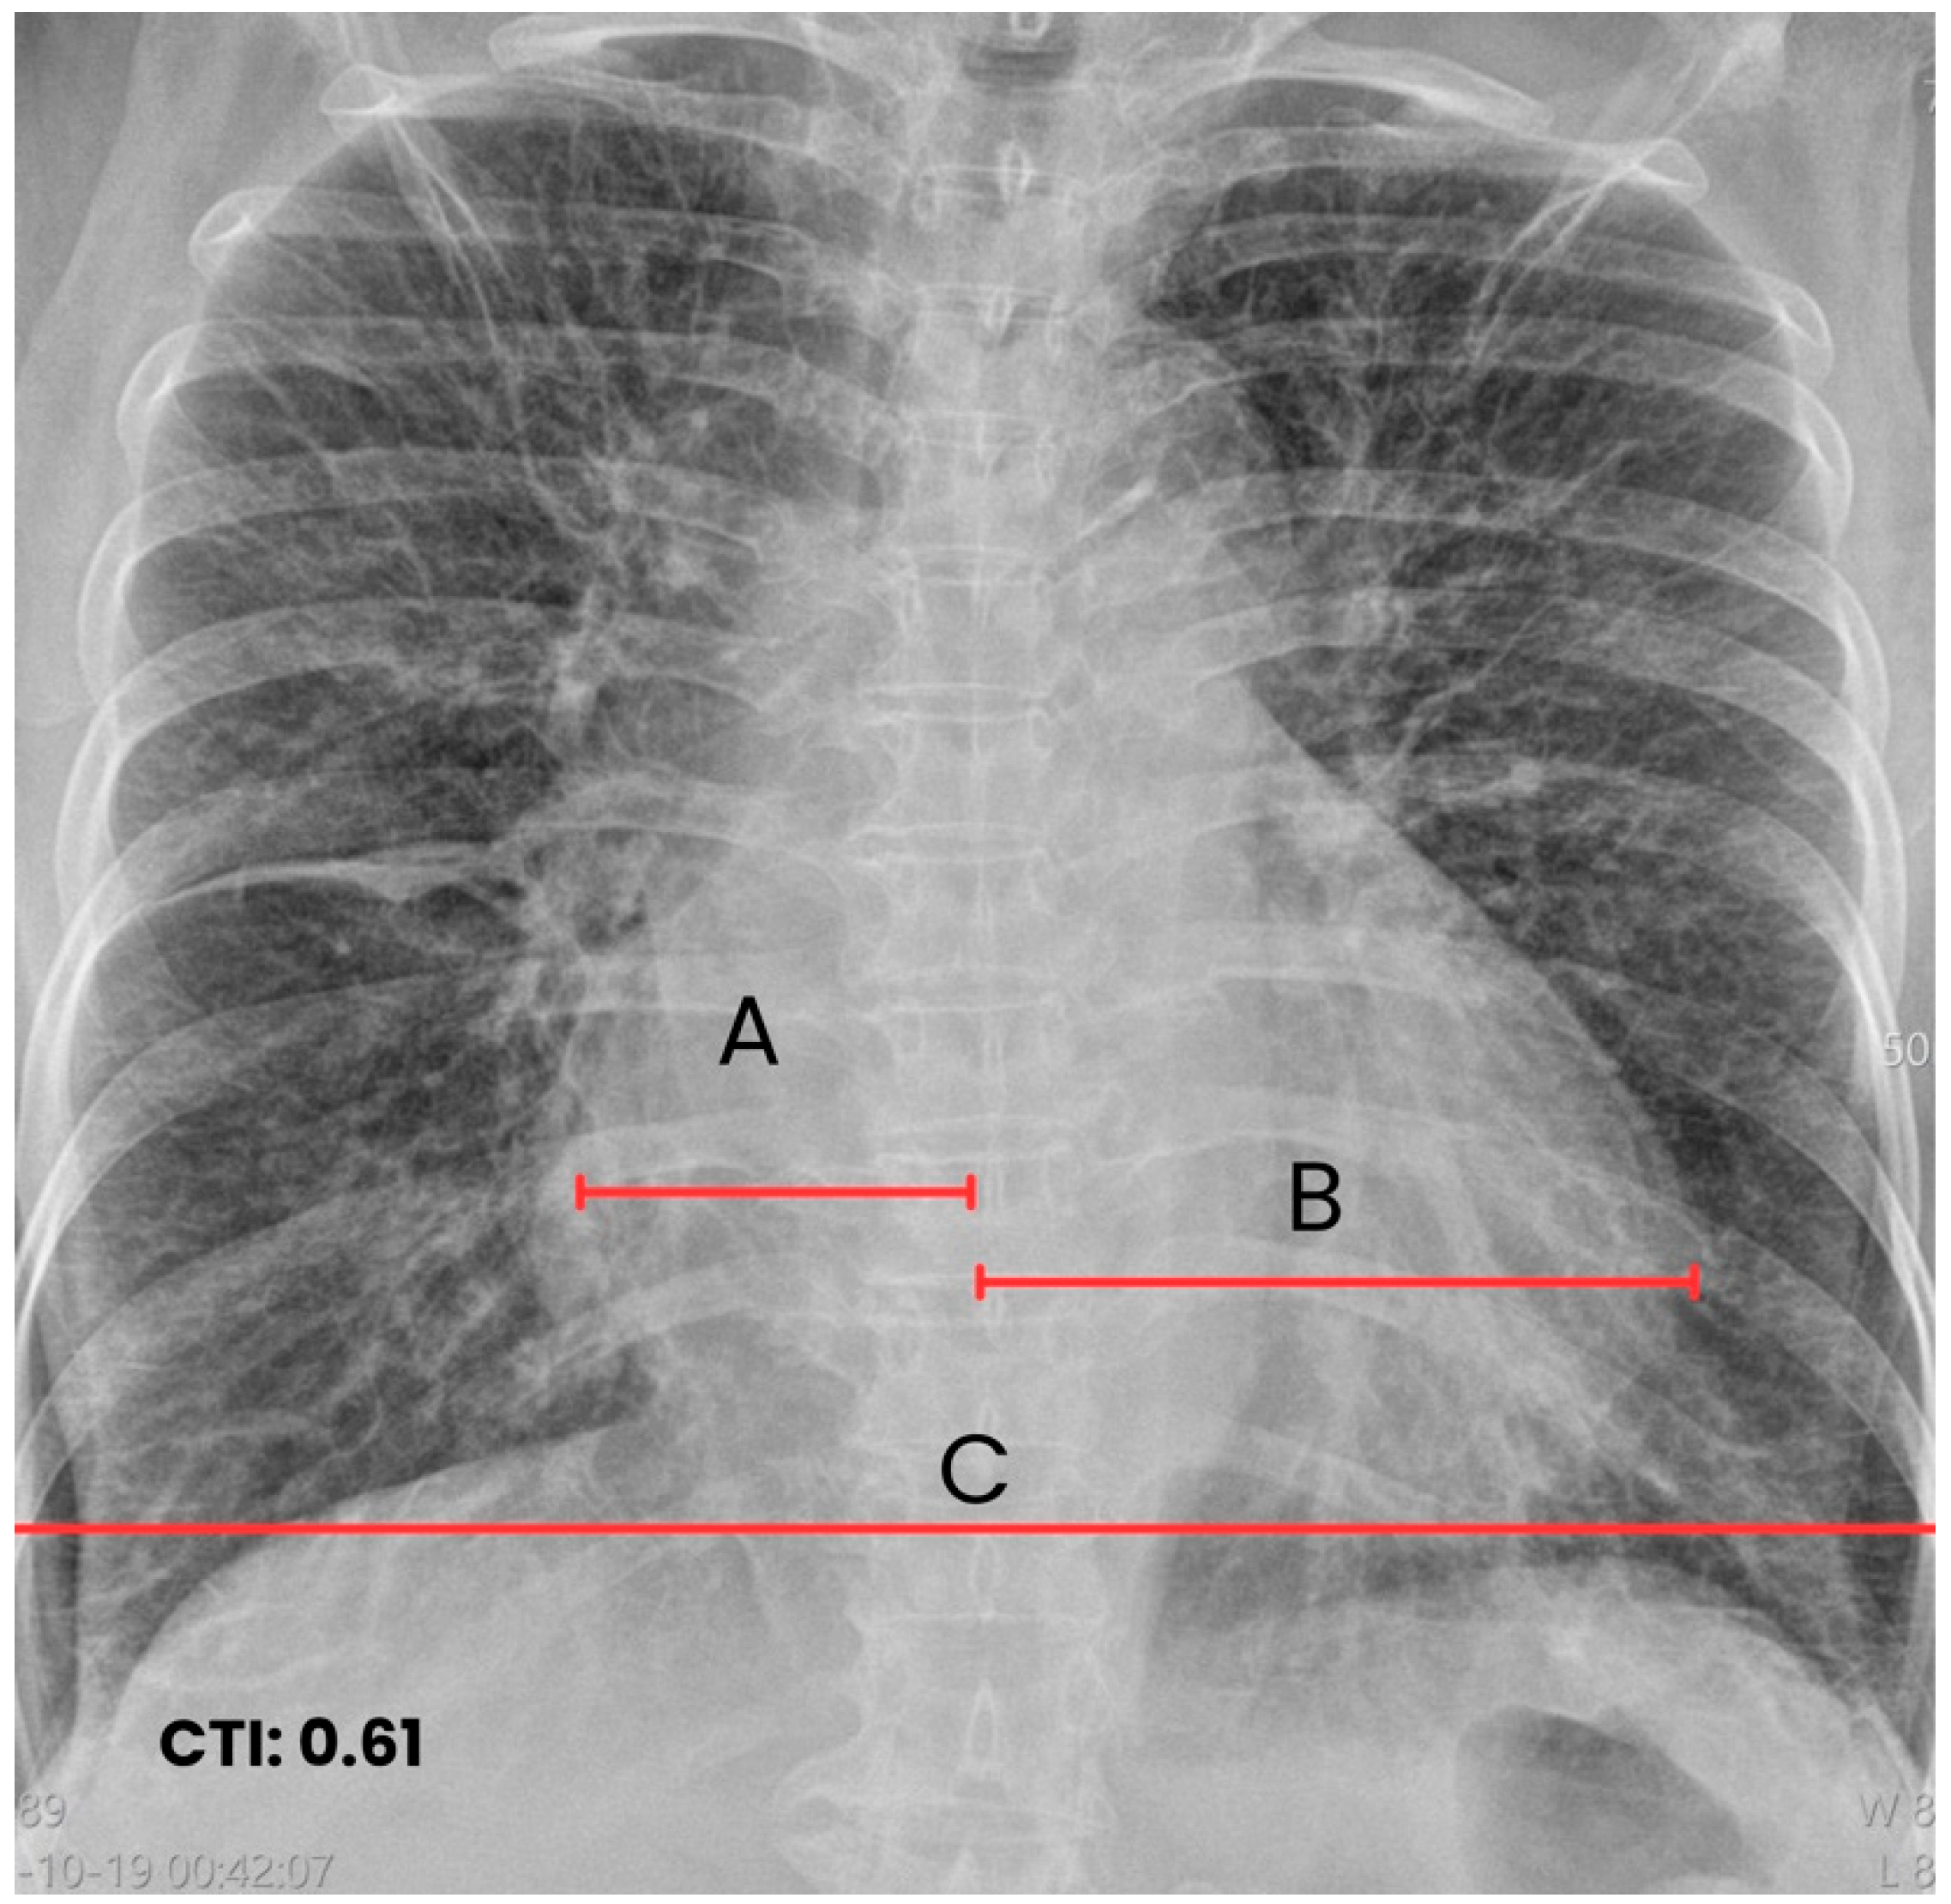

| T0 + ED arrival | Emergency Dept. | Stroke code activated. NIHSS 9, GCS 11/15, premorbid mRS 0. | ECG: typical atrial flutter with rapid ventricular response. Non-contrast CT brain: right MCA ischemic stroke (ASPECTS 7), no hemorrhage. | Supportive acute stroke care | Acute ischemic stroke suspected/confirmed |

| Early inpatient workup (Day 0) | Hospital | Suspected cardioembolic source in context of arrhythmia/Chagas cardiomyopathy. | TTE: severe LA dilation + mobile LA thrombus; LVEF 45%. Labs: no major abnormalities; mild troponin I and NT-proBNP elevation. | — | Cardioembolic mechanism supported |

| Hospital course (after hemorrhage exclusion) | Hospital | Secondary prevention initiated. | Risk scores documented: CHA2DS2-VASc 3, HAS-BLED 1. | Warfarin anticoagulation started; transition to oral amiodarone. | Ongoing stability |